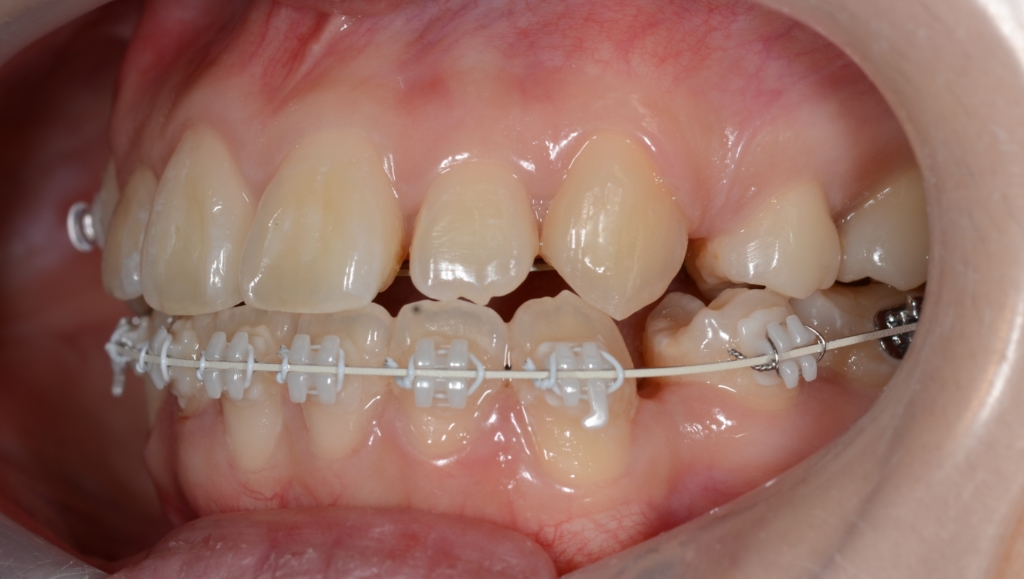

マルチブラケットシステム(ハーフリンガル type)で矯正を開始。

【1年経過】

【残る隙間を閉じて仕上げへ】